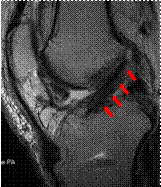

再建された膝前十字靱帯